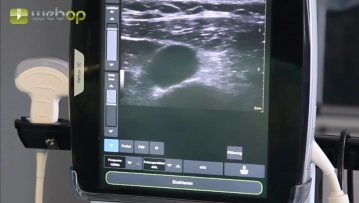

Tras la desinfección de la piel y la cobertura estéril, se realiza la ecografía dúplex con el fin de localizar la vena yugular interna. En el clip no se representa la anestesia local, que abarca el lado del cuello elegido, todo el canal subcutáneo y el posterior punto de salida percutáneo del catéter infraclavicular. Por regla general, se necesitan 10-15 ml de anestésico local (p. ej. Xylonest® al 1 %).

Ecografía dúplex de la vena yugular interna derecha, anestesia local

Ajustes de sonido Bajo control ecográfico se realiza la punción de la vena yugular interna con la cánula de Seldinger. Introducción del alambre guía.